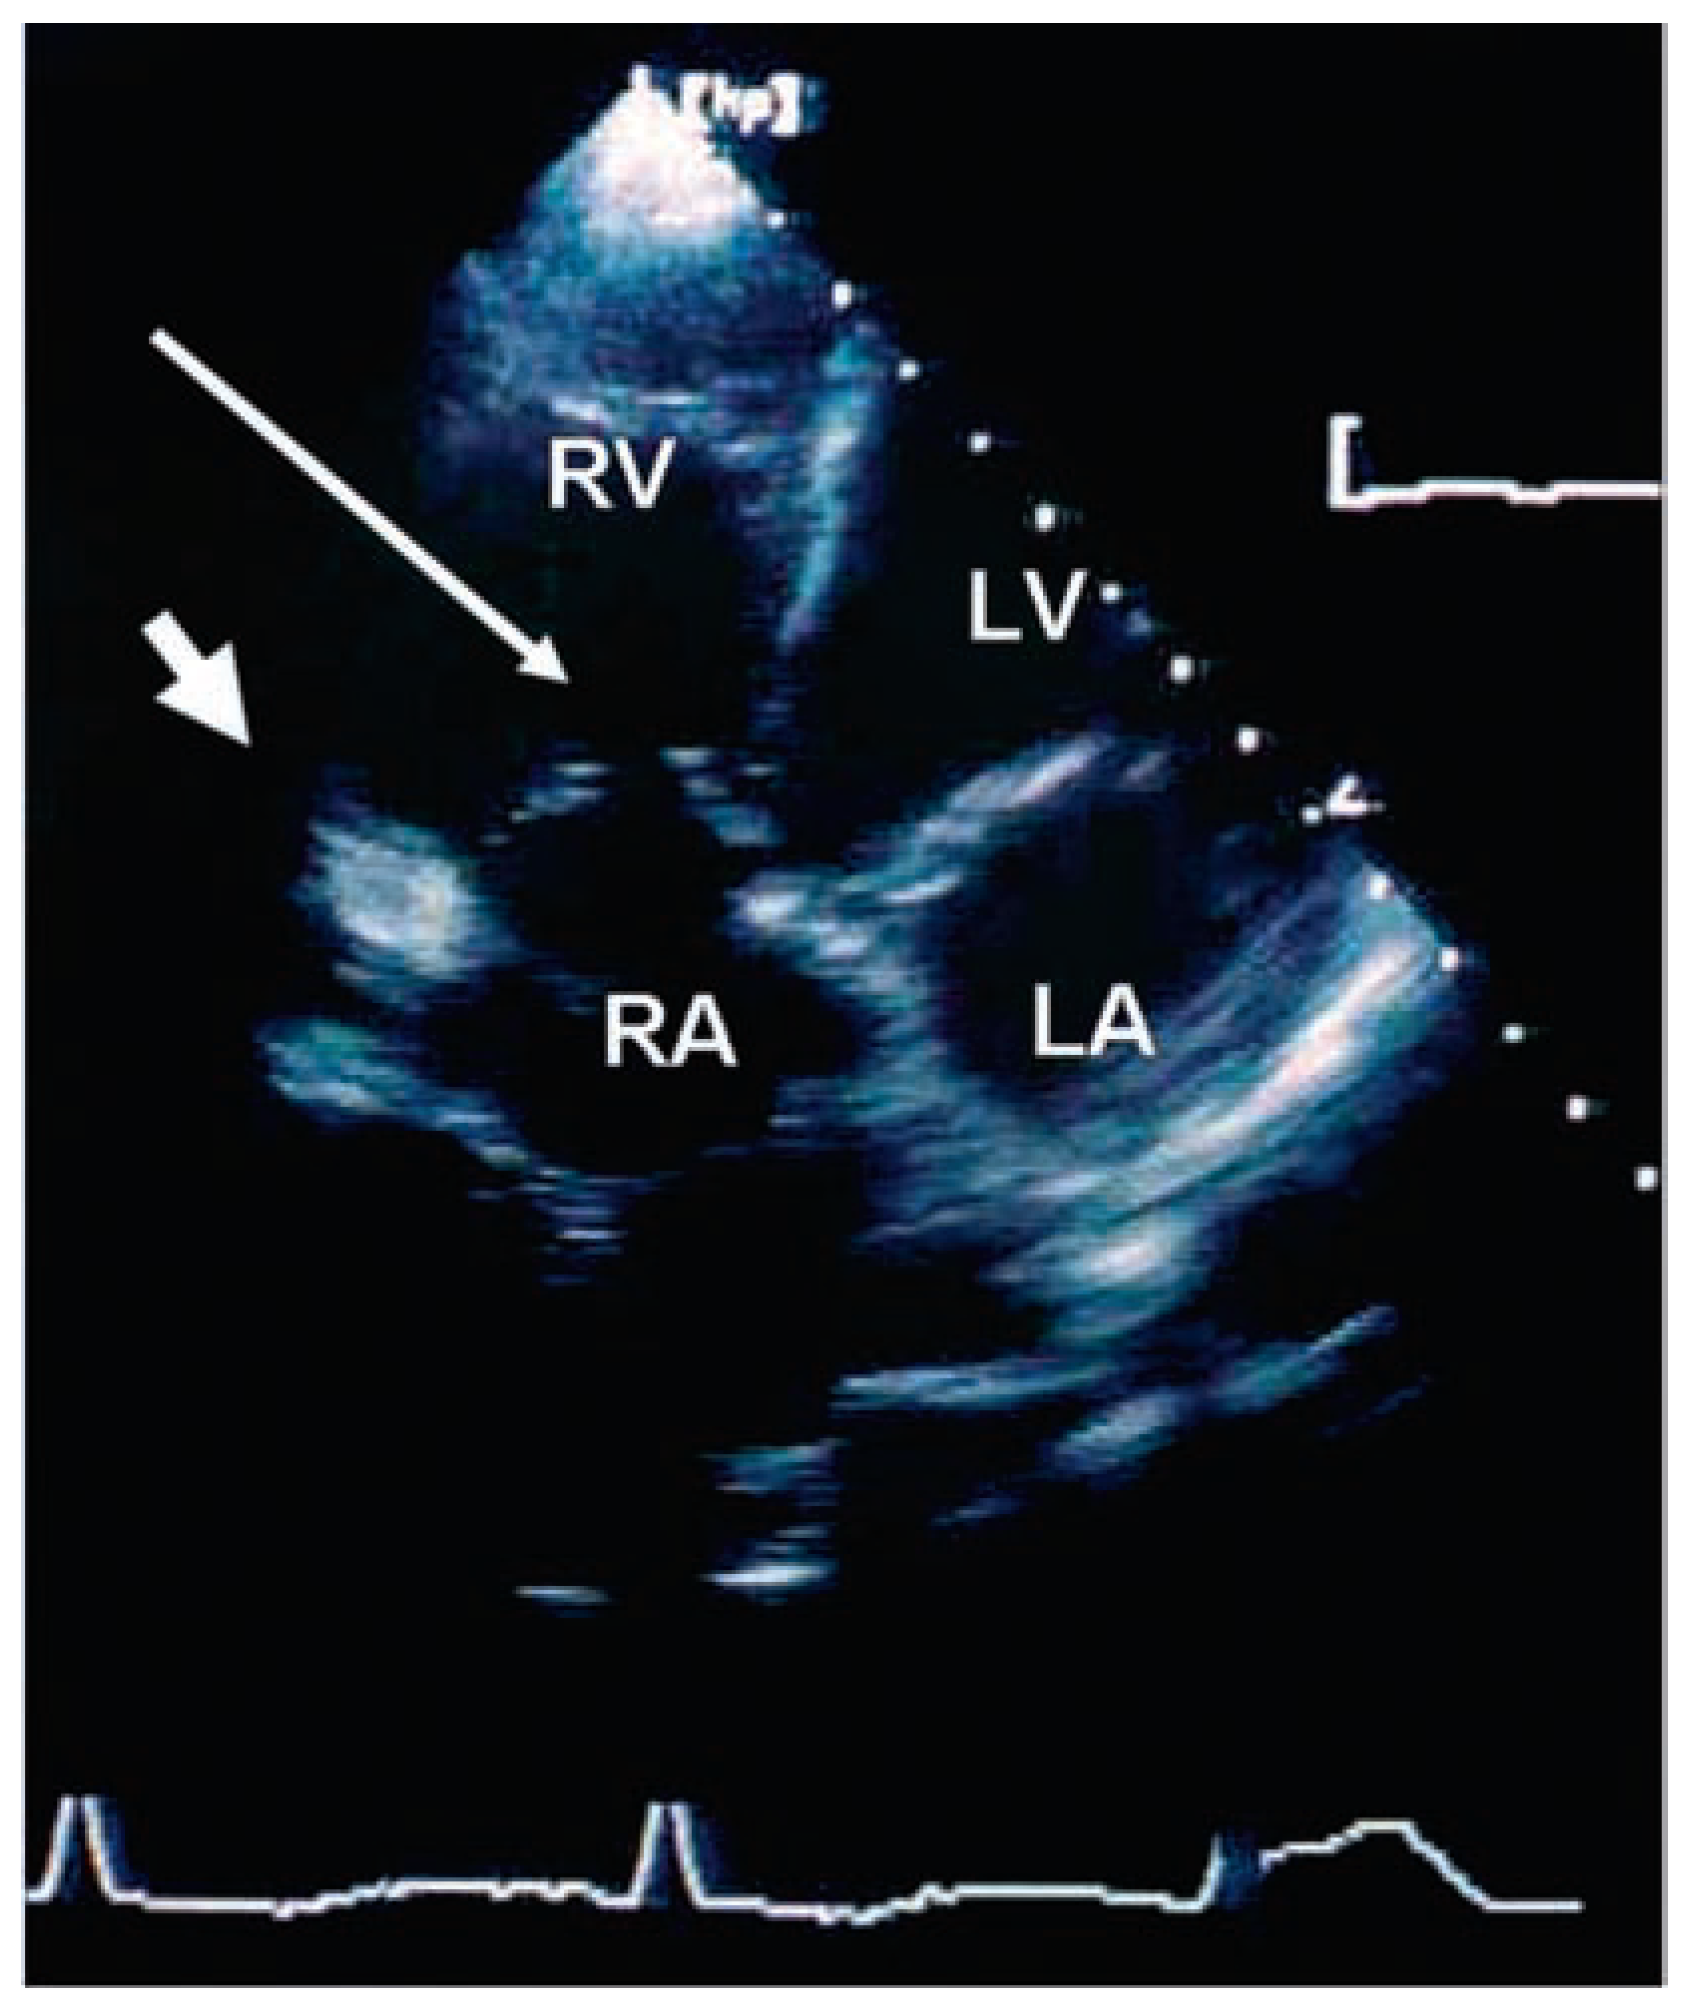

Echocardiographic findings

|

Pericardial disease

Valvular heart disease